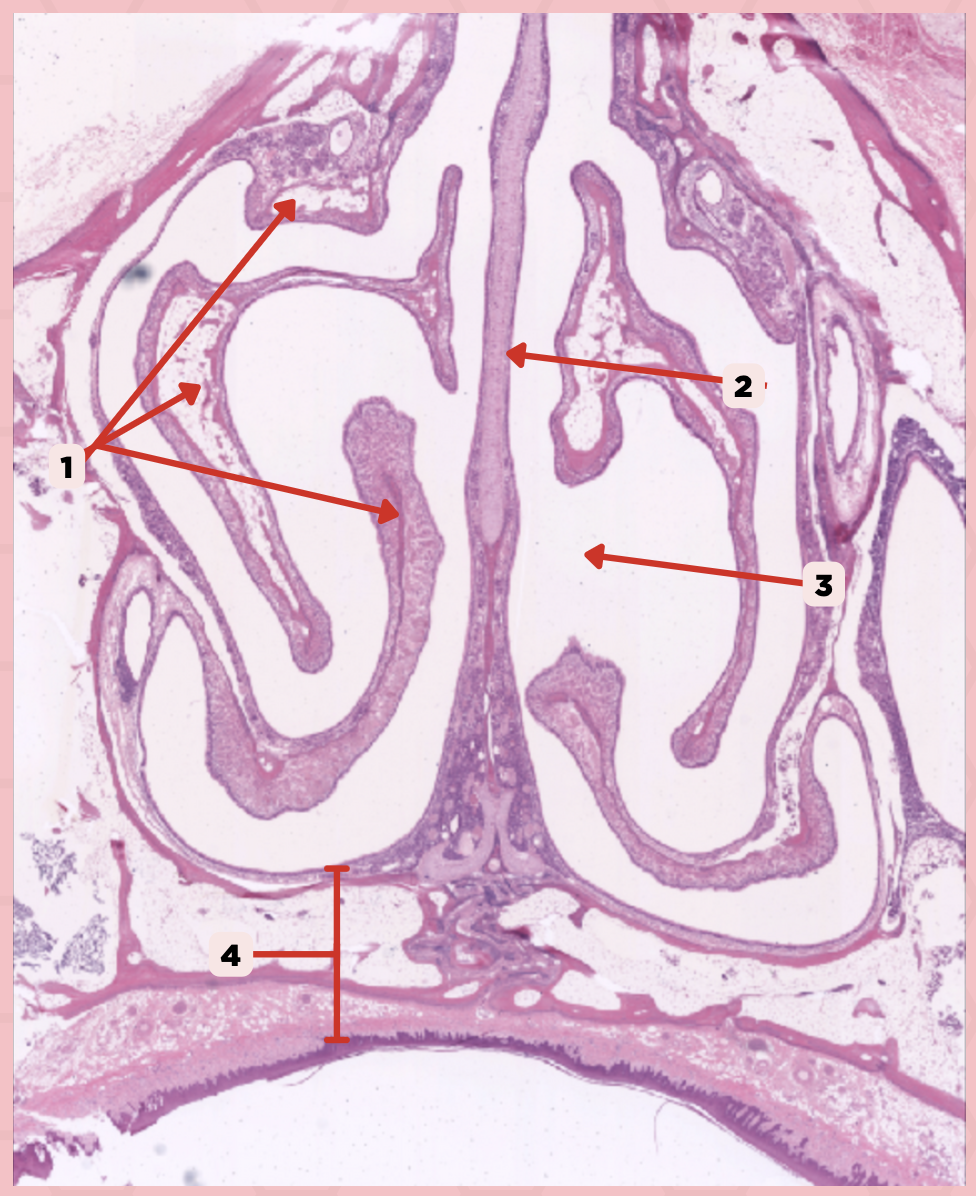

Nasal Cavity

What are the spaces found immediately lateral to #2?

Nasal Turbinates (conchae)

Identify the structure labeled as 1.

Nasal septum

Identify the structure labeled as 2.

Nasal cavity

Identify the structure labeled as 3.

Hard palate

Identify the structure labeled as 4.

Mucosal Associated Lymphoid Tissue (MALT)

What time of lymphocyte is numerous in the nasal cavity?